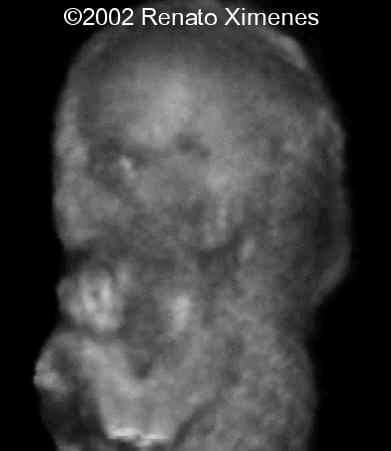

This second trimester fetus demonstrates a very thick nuchal edema with cystic hygroma:

case0072-1

case0072-2

The 3D reconstructions nicely demonstrate the webbing of the neck, low-set ears and micrognathia.

case0072-10

case0072-9